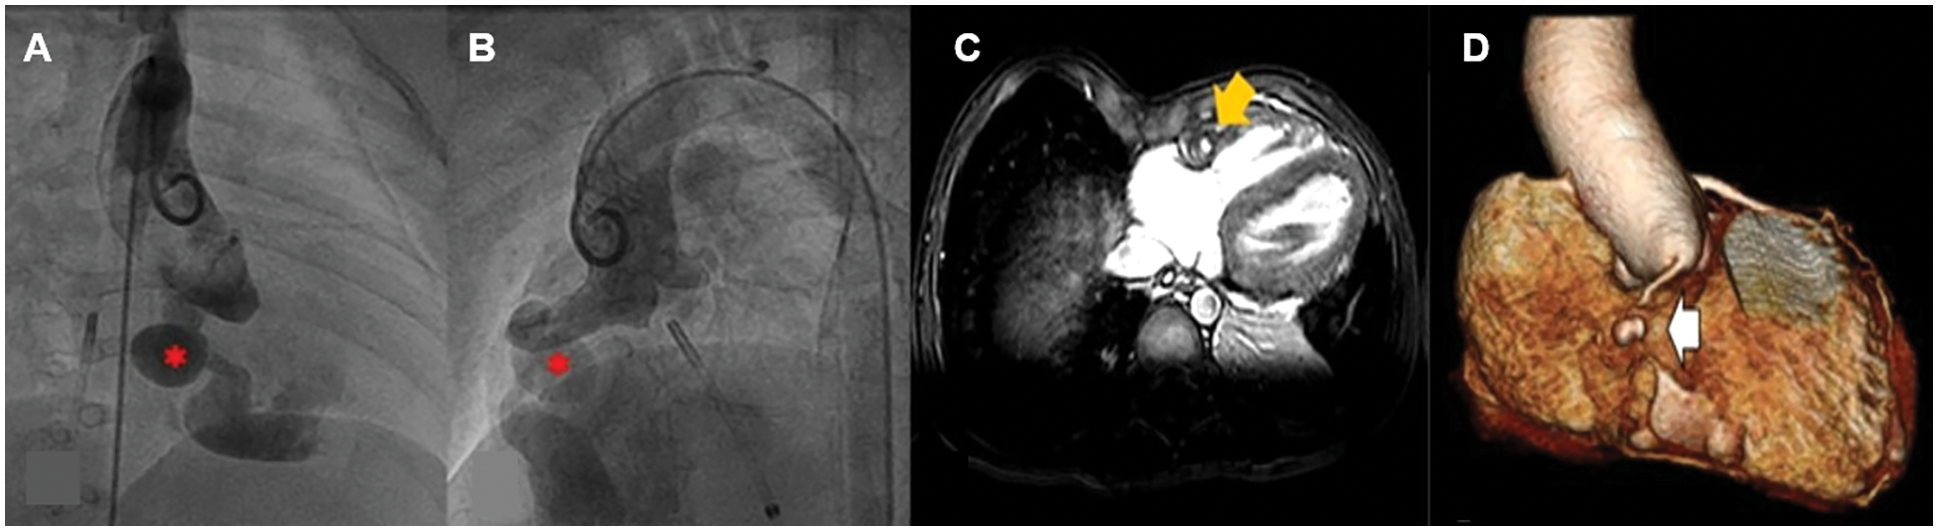

Primary treatment with SC was chosen for 7 patients [median age at diagnosis of 1 month (range 4 days–7 years)], all of whom had isolated CCAF with symptoms of heart failure. All of the preoperative TTEs showed good LV function. The median age at the time of the repair was 2 years (range 1 month–9 years). A complex fistula (i.e., 2 openings) was noted in one patient. All patients had dilated fistulous tracts and one had the drainage site to the coronary sinus (Fig. 2). The surgical procedures included surgical ligation/direct closure (n = 5), pericardial patch closure (n = 1), and fistulous ligation with aneurysmorraphy (n = 1). In addition, three patients underwent surgical ligation subsequent to the attempted PC, as previously described. Ten patients who underwent SC had no operative mortality. The median cardiopulmonary bypass and cross clamp time was 34 min (range 15–86 min) and 15 min (range 10–54 min), respectively. Postpericardiotomy syndrome and transient asymptomatic ST depression was noted in one patient. Average hospital length of stay was eight days (including a pre-operative day). At the median time of follow-up [3.3 years (range 0.1–8 years)], the ten patients survived without ischemic heart or heart failure symptoms. Four patients had postoperative CCT and CMR surveillance. Two patients with post-operative thrombus formation in the dilated fistulous tract had a stenosis of the distal coronary artery without perfusion deficit and they had preserved LV function. Characteristics of the original CCAF were complex: 2 large openings in 1 patient and a large-diameter drainage site with a dilated distal coronary artery in one patient (Figs. 3 and 4) (Table S1).

Figure 3: Pre- and post-operative cardiovascular computerized tomography (CCT) in a one-year-old girl with a large congenital coronary artery fistula (CCAF) from the right coronary artery (RCA) to the right ventricle (RV); A, B. Pre-operative CCT demonstrating the large tortuous RCA and the CCAF from RCA to RV (red arrow); C. Post-operative CCT showing total RCA occlusion (white arrow) compared to pre-operation (blue arrow) in B

Figure 4: Pre-operative aortic root angiography in a patient at one year of age and cardiac image at 6-year post-operation with large congenital coronary artery fistula (CCAF) from the right coronary artery (RCA) to the right ventricle (RV); A, B. Aortic root angiography showing aneurysmal dilation of RCA and CCAF from proximal RCA to RV (*); C, D. Post-operative CMR showing filling defect (yellow arrow) at the mid-RCA due to intraluminal thrombus. The 3-D reconstruction shows a small, mid-RCA aneurysm (white arrow). No RCA flow was observed distal to the aneurysm